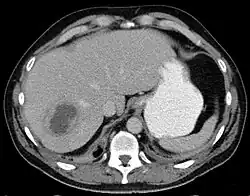

Ein Leberabszess ist eine abgegrenzte Eiteransammlung (Abszess) im Lebergewebe. Er kann primär durch Bakterien (z. B. Escherichia coli, Staphylococcus aureus), parasitische und einzellige Infektionserreger (z. B. solitäre Leberabszesse verursachende Art Entamoeba histolytica bei der Amöbenruhr) oder sekundär nach einem operativen Eingriff entstehen. Die Erreger können über das Blut (hämatogen), die Lymphe (lymphogen) oder die Gallengänge (cholangiogen aus einer eitrigen Cholangitis) in die Leber vordringen. Über die Pfortader können Erreger von entzündlichen Herden (zum Beispiel bei eitriger Appendizitis) ebenfalls in die Leber gelangen und so Abszesse entstehen lassen.[1]

Die Symptome eines Leberabszesses sind meist hohes Fieber, Leberdruckschmerz, Übelkeit und Erbrechen, Gelbsucht und Anämie. Die Diagnose wird mittels Ultraschalluntersuchung und einer CT-Aufnahme gesichert. Die Therapie erfolgt medikamentös (durch hochdosierte Antibiotikagaben), durch eine perkutane Drainage oder durch chirurgische Entfernung der Abszesshöhle eventuell durch eine Segmentresektion. Als Komplikationen eines Leberabszesses gelten eine Sepsis oder Ruptur der Abszesshöhle mit Durchbruch in die freie Bauchhöhle und nachfolgender Bauchfellentzündung.